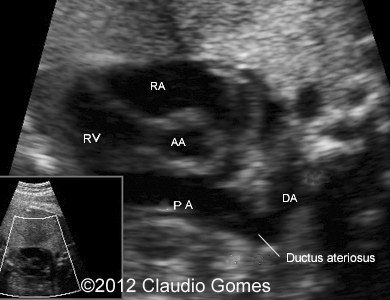

Images 6, 7: 37 weeks, four-chamber and five-chamber view with the aorta and Azygos vein

f3

Fig7